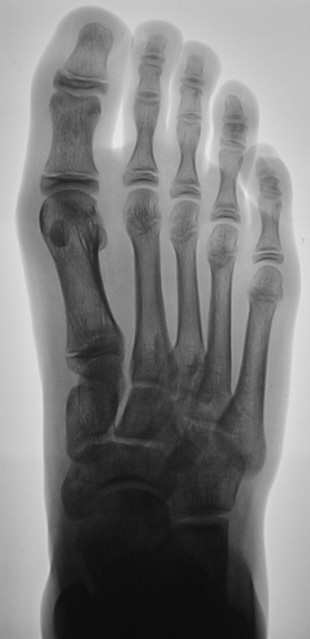

Травма. Пациент направлен врачом хирургом на рентгенографию переднего отдела стопы. Произведено исследование. Интерес у нас вызвал 1 палец. Какие мнения будут уважаемые коллеги?

Похоже на перелом средней фаланги

Настолько качественная рентгенограмма, что передний край суставной поверхности дистального эпифиза средней фаланги первого пальца, который имеет форму буквы V, симулирует линию перелома...

Костно-травматических изменений у отрока не выявлено.

Я бы не исключила перелом, только не средней, а основной фаланги, средней то у первого пальца нет.